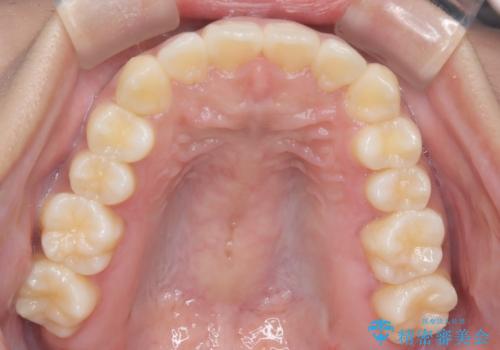

【インビザライン】笑ったときに目立つ八重歯をなおしたい

- 笑ったときに八重歯が見えることを主訴に来院されました。

下の前歯が一本足りない患者様でしたので、シミュレーションを作り、事前に患者様と治療ゴールのイメージをしっかり共有したうえでインビザラインを用いて治療を行っています。

奥歯を後ろのほうに動かすことで、前歯も少し下がることができ、矯正後の口元も満足していただきました。

下顎の前歯が一本ない場合は上下の正中は合いません。